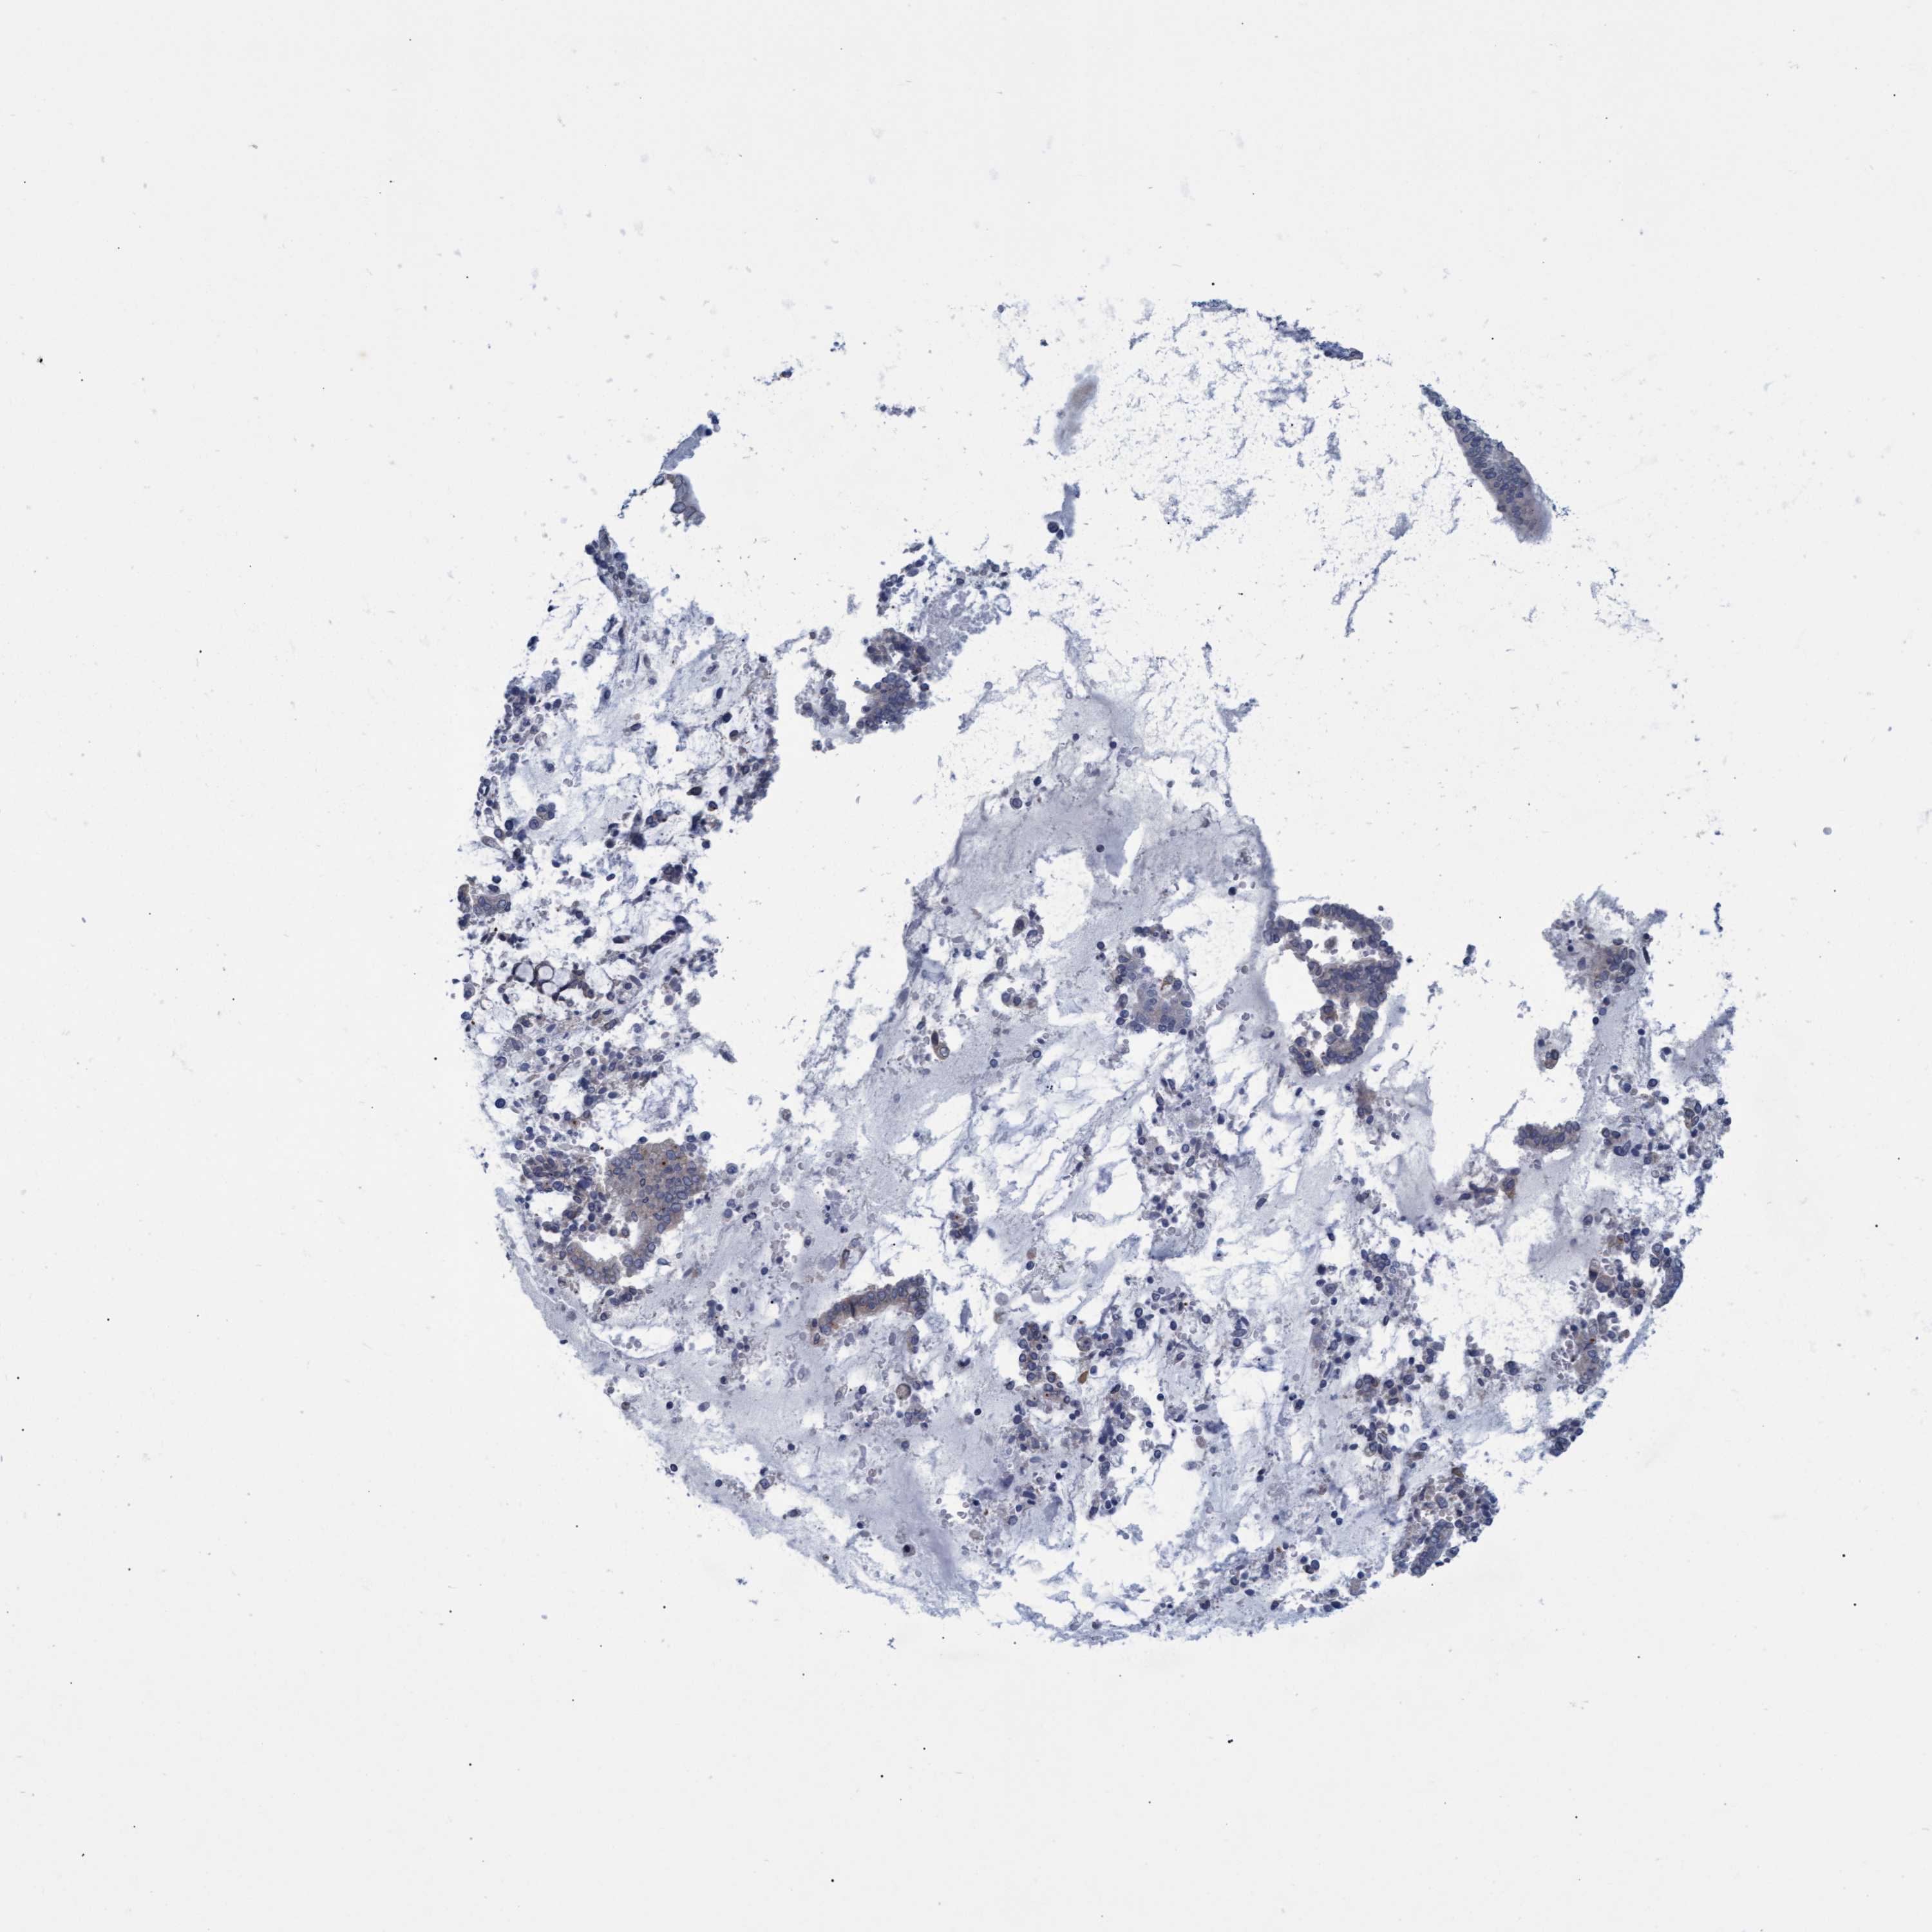

CERVICAL CANCER - Protein expressioni

A mouse-over function shows sample information and annotation data. Click on an image to view it in a full screen mode. Samples can be filtered based on level of antibody staining by selecting one or several of the following categories: high, medium, low and not detected. The assay and annotation is described here.

Note that samples used for immunohistochemistry by the Human Protein Atlas do not correspond to samples in the TCGA dataset.

Antibody stainingi

Antibody staining in the annotated cell types in the current human tissue is reported as not detected, low, medium, or high, based on conventional immunohistochemistry profiling in selected tissues. This score is based on the combination of the staining intensity and fraction of stained cells.

Each image is clickable and will lead to virtual microscopy that enables deeper exploration of all samples and also displays staining intensity scores, fraction scores and subcellular localization as well as patient and tissue information for each sample.

Antibody CAB022647

Staining

High

Medium

Low

Not detected

Intensity

Strong

Moderate

Weak

Negative

Quantity

>75%

75%-25%

<25%

None

Location

Nuclear

Cytoplasmic/membranous

Cytoplasmic/membranous,nuclear

Squamous cell carcinoma, NOS

Adenocarcinoma, NOS